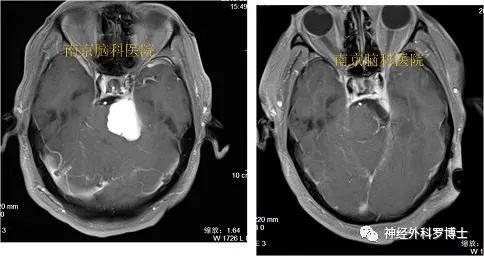

术前磁共振检查诊断:右侧岩尖脑膜瘤、继发性右侧TN;

术前MRI提示肿瘤位于右侧岩尖,压迫脑干及三叉神经。

术前磁共振轴位增强

术后增强示肿瘤全切